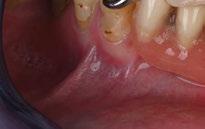

Acude a la consulta un paciente masculino de 35 años exigiendo cambios en la estética de sus dientes. El examen intraoral clínico y fotográfico reveló pérdida de estructura dentaria con facetas de desgaste en dientes anterosuperiores e inferiores, acentuándose hacia zonas oclusales de dientes posteriores.

El diagnóstico evidenció que el paciente presentaba alteración en la dinámica de la guía anterior por el desgaste de los bordes incisales, con pérdida de dimensión vertical oclusal (VDO), alteración del plano de oclusión y relaciones interoclusales inestables (Figuras 1 y 2)

Figura 1. Caso inicial. Figura 2. Vista oclusal superior.